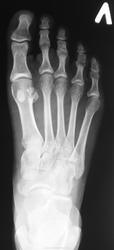

Молодая женщина. Беспокоят боли в ступнях по подошвенной поверхности, больше слева.

Правая стопа сделана больше для сравнения.

Остеохондропатия сесамовидной кости 1 пл/фал.сустава левой стопы.

Весьма патогномоничной является рентгенологическая картина третьей стадии заболевания - стадии фрагментации. Пораженный отдел кости уже не дает гомогенной тени, а состоит из нескольких темных бесструктурных изолированных фрагментов неправильной формы. Светлые участки, на фоне которых видны эти фрагменты, соответствуют разрастаниям соединительной ткани и хряща между некротическими массами. Высота пораженного отдела кости уменьшается. Длительность третьей стадии составляет от полугода до двух с половиной лет, а иногда и более. Вероятно Валентин Львович, дама не сидит, а ходит, постоянная нагрузка веса тела делает свое дело.

"На рентгенограмме-типичная дезорганизация структурного рисунка несколько иногда увеличенной косточки с фрагментацией её тени.Регенеративные явления выражены незначительно,полного восстановления стуктуры не бывает"-С.А.Рейнберг т2 стр286.      (несколько иногда( в тексте))-это вероятно в данном случае.

несросшийся перелом сесамовидной слева